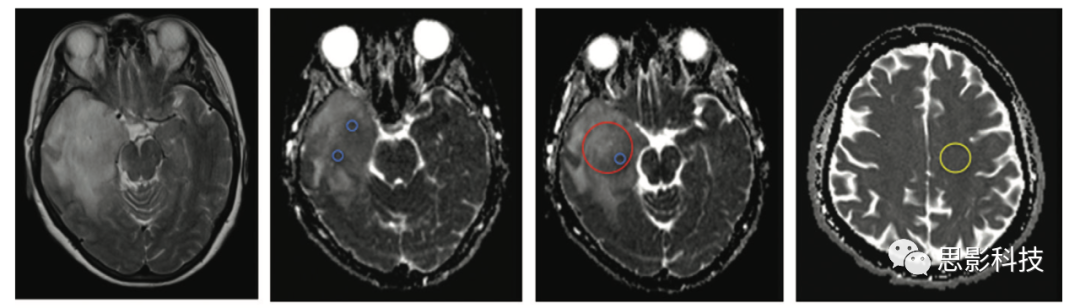

异柠檬酸脱氢酶(IDH)基因的变异,可用来定义绝大部分(>70%)慢生长型胶质瘤。对于胶质瘤的基因分型,目前尚缺乏可以稳定实现的MRI生物标记。基于T1、T1CE、T2和FLAIR序列,可以提取一系列肿瘤相关的解剖特征,但不足以作为可靠的生物标记。为此,来自伦敦大学学院神经病学部的John Maynard等人尝试加入DWI指标(如ADC,表观弥散系数),来提升影像特征的预测效果。

作者汇集了一批跨度10年(2008~2019)的病患数据(共计290被试,有完整的基因型信息),人工提取了这些被试的解剖特征,并计算了DWI指标:ADCmin、ADCmean、ADCnawm,也就是肿瘤区域的最小表观弥散系数、平均表观弥散系数、正常白质内的表观弥散系数。联合解剖特征和DWI指标,使用Logistic 回归模型进行预测,结果发现,基因型分类准确率可达80%以上。该文提示我们,在肿瘤分级与分类应用中,常用的序列是T1、T1CE、T2、FLAIR以及灌注相关的序列,或许加入DWI的信息,也能提供一定的帮助。